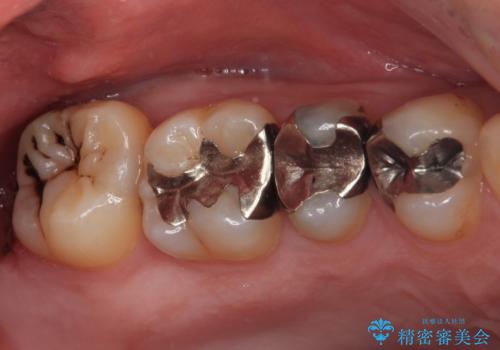

銀歯をなくしたい 全顎的なむし歯治療

- 銀歯やむし歯でものが挟まるところが気になるとのことで来院された患者様です。

左上の奥歯は神経が失活しており、根管治療が必要な状態でした。

その他は銀歯のインレー(部分的な詰め物)が装着されており、それらはむし歯を除去した後にセラミックインレーにて修復治療を行い、左下と根管治療を行う左上の奥歯はオールセラミッククラウンにて補綴治療を行うこととしました。